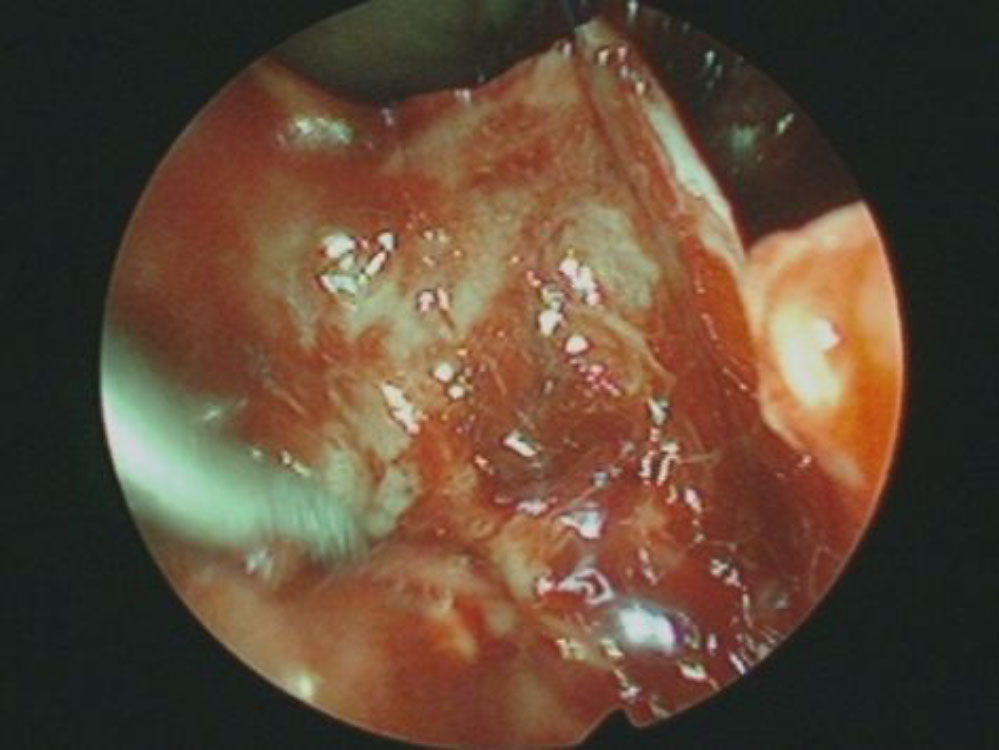

No.’25_102 摘出 前

No.’25_102  摘出 中

下垂体腺腫

頭蓋内腫瘍摘出術